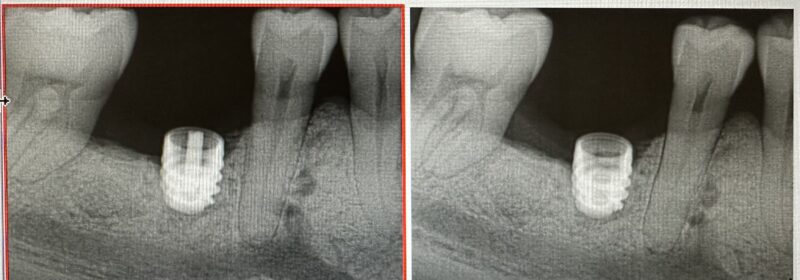

The case I am sharing has been quite challenging for me restoratively. Patient was referred out for implant placement #31. It is a Nobel implant WP. First time I restored it, within a week of insert abutment fractured. Fortunately, retrieving the abutment screw was not that difficult. When I inserted the first time I did know something is…

This one is a bit tough. I say that because it looks like it was a little difficult on the surgical aspect with minimal bone height. It always seems to work out this way–in the cases where you wish to have no problems, you often encounter them.

It’s okay though. Let’s try to get to the bottom of this.

First: I understand you cemented the crown…